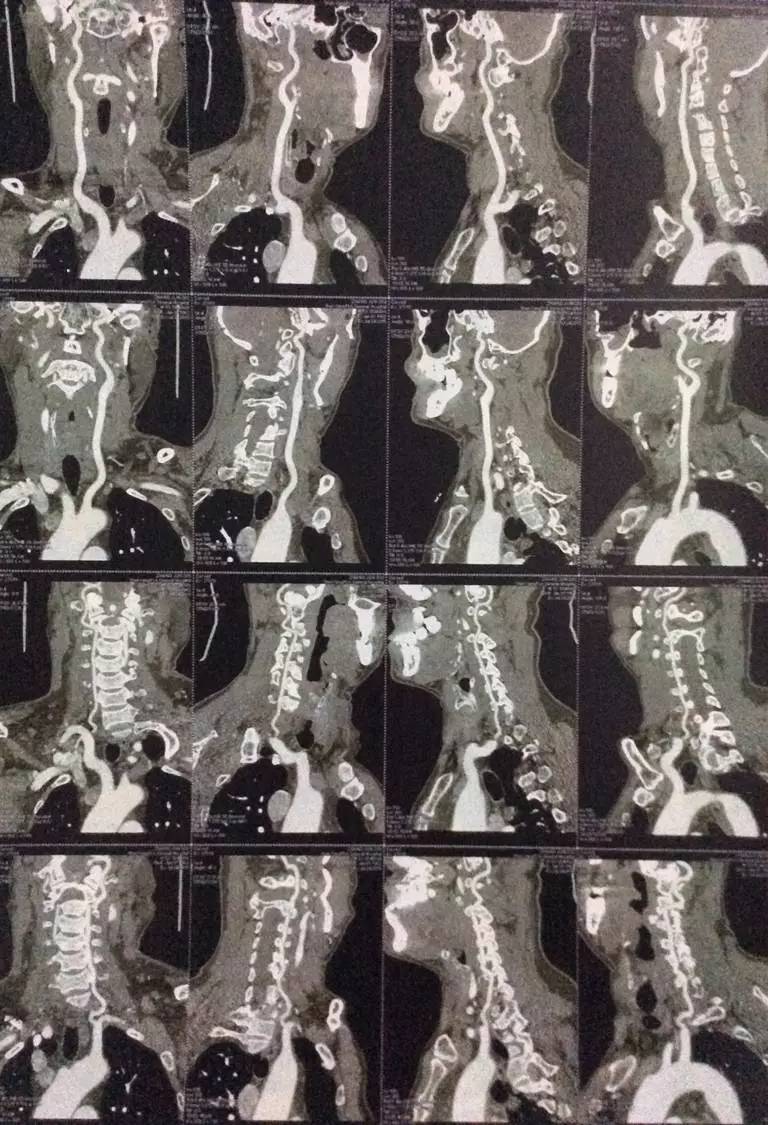

右侧椎动脉颅内段局限性显示纤细,余脑血管未见明显异常。

脑干及右侧基底节见点片状低密度,部分病灶边界清晰,余脑内未见明显异常。

右颈内动脉近段混合斑块形成,管腔狭窄约20%;右椎动脉起始处非钙化斑块形成,管腔狭窄约40-50%,余颈部血管未见明显异常。